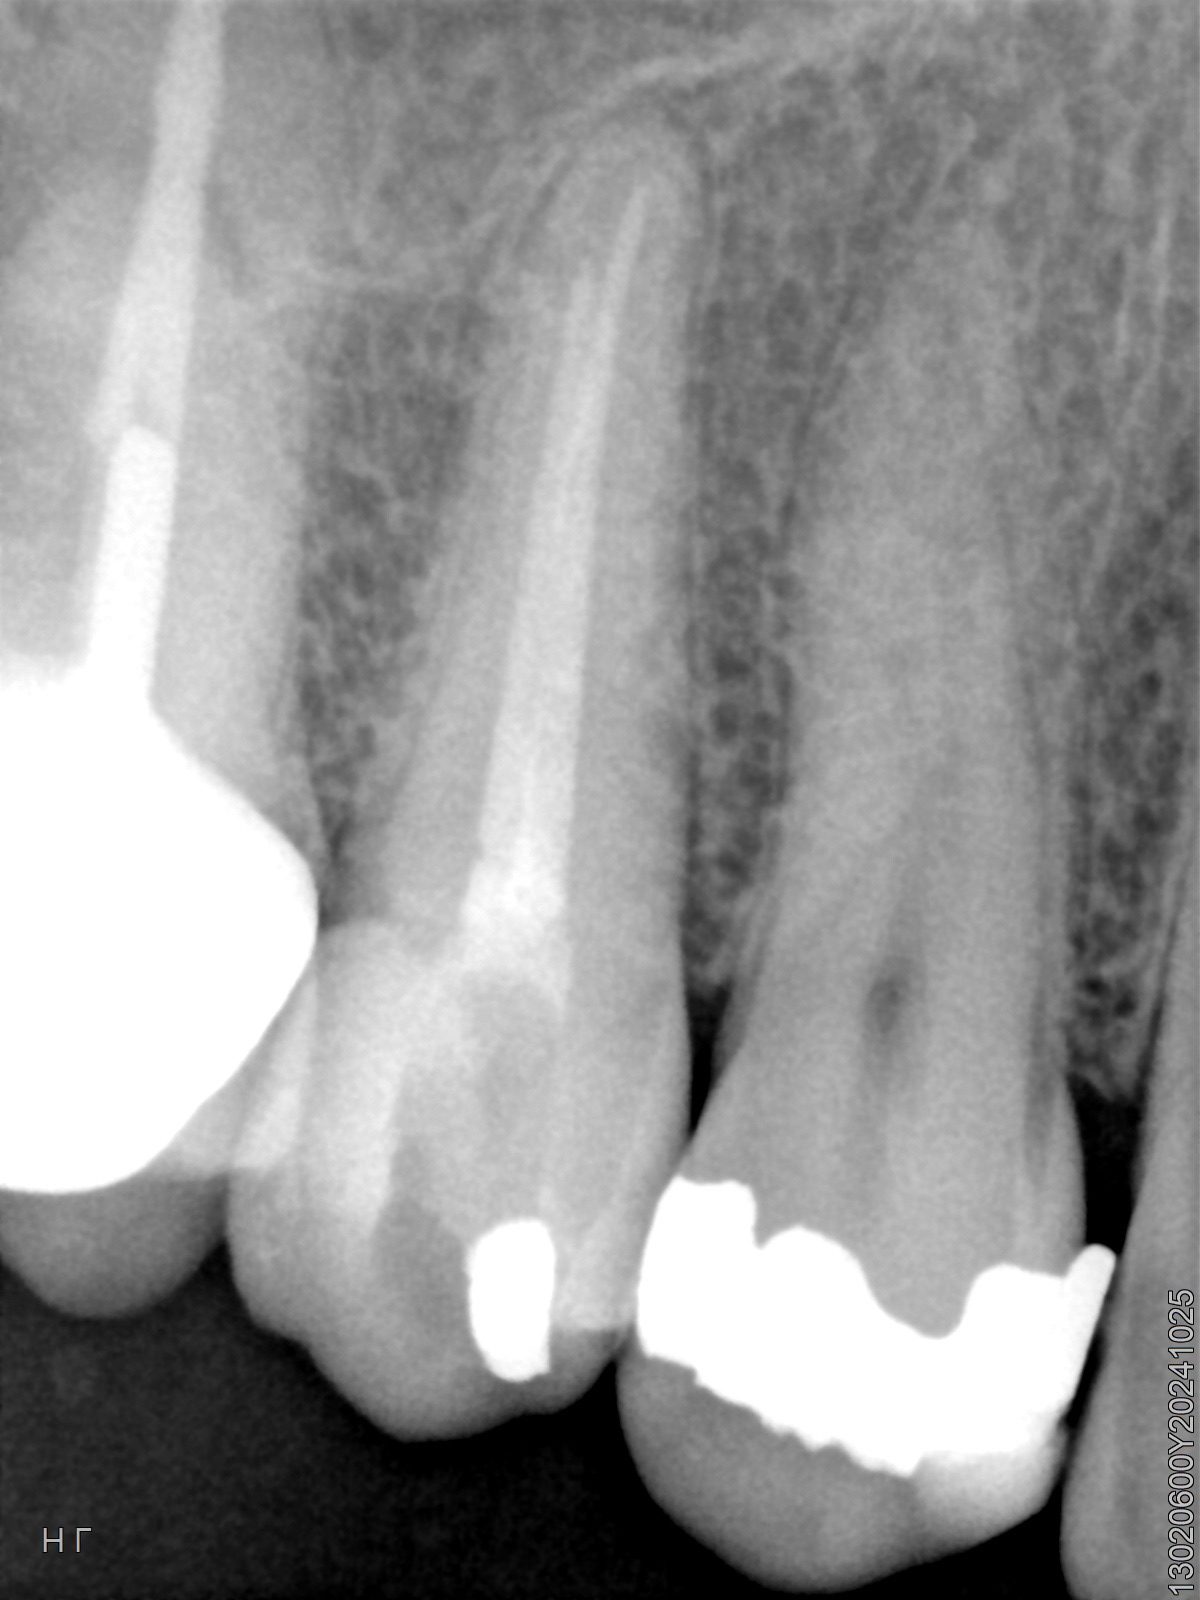

Veja alguns casos de sucesso